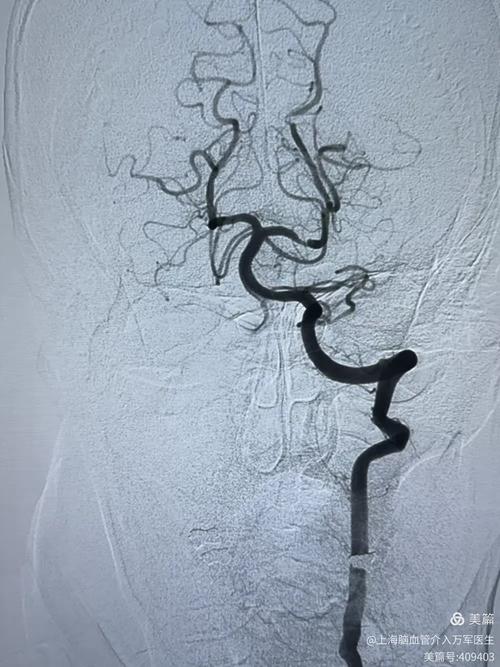

- 头颅CTA/MRA/DSA:必要时(如症状变化、评估是否需要手术)进行脑血管成像,精确评估狭窄部位和程度。

第四支柱:评估是否需要介入或手术治疗(二线方案)

对于药物治疗后仍反复发作,或狭窄程度非常严重(如超过70%)的高危患者,医生可能会建议进行介入或手术治疗。